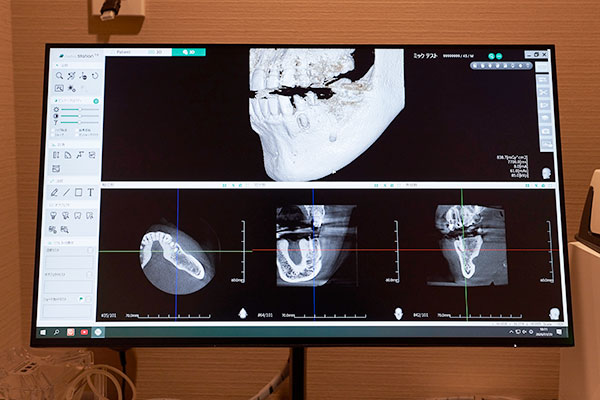

目に見えないリスクを可視化

外科処置において、目に見えない神経の位置や血管の走行、骨の厚みを正確に把握することは安全の絶対条件です。当院では歯科用CTを完備しており、3次元的な画像診断により抜歯や手術のリスクを徹底的に排除します。平面のレントゲンでは判別が難しかった複雑に曲がった根の形や、顎の骨との位置関係を詳細に分析することで、手術時間の短縮と術後の腫れや痛みの軽減につなげます。